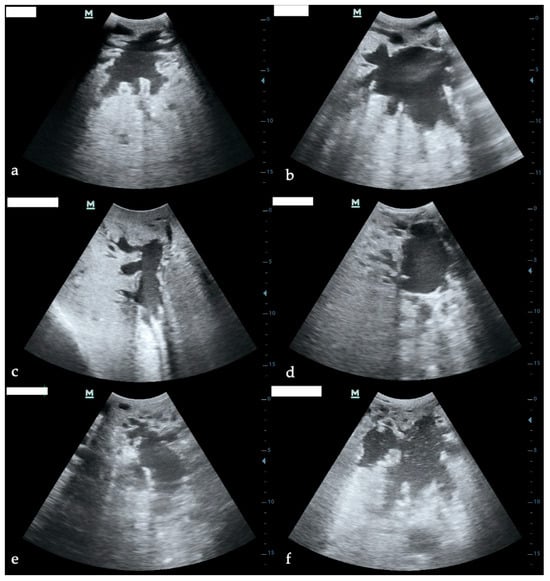

Ultrasonographic examination of the glandular cistern proved to be feasible under field conditions and was easily performed in all animals. Adequate visualization of the glandular cistern was consistently achieved without the need for shaving, using only ultrasound gel applied directly to the skin. The cistern could be clearly visualized in all quarters at each time point (T0, T1, T5) (Figure 1). The average time required to perform transcutaneous ultrasonography of the glandular cistern was 57 ± 29 s for the longitudinal projection and 46 ± 32 s for the transverse projection. The maximum duration recorded for a complete ultrasonographic examination was 185 s.

Figure 1. Ultrasonographic images of bovine glandular cisterns. (a,b) Healthy quarters in transverse (a) and longitudinal (b) sections. (c,d) Subclinical mastitis (SCM) quarters in transverse (c) and longitudinal (d) sections. (e,f) Clinical mastitis (CM) quarters in transverse (e) and longitudinal (f) sections.

At baseline (T0), the transversal section showed larger cisternal areas in contralateral healthy quarters compared to subclinical and clinical cases. Specifically, the median transversal area was 36.8 mm2 (25.5–44.8) in contralateral healthy quarters, 31.2 mm2 (19.5–38.3) in subclinical cases, and 29.3 mm2 (22.5–42.0) in clinical mastitis. A similar pattern was observed in the longitudinal section, where median cistern areas were 36.6 mm2 (26.8–46.1) in contralateral healthy quarters, 31.6 mm2 (21.4–38.2) in subclinical quarters, and 30.2 mm2 (22.0–39.7) in clinical mastitis. The results of the glandular cistern area across all time points and groups are presented in Table 1.